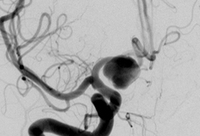

Three-dimensional catheter angiogram showing a basilar tip aneurysm

From: Sellar M. Practical Neurology. 2005;5:28-37. Used with permission